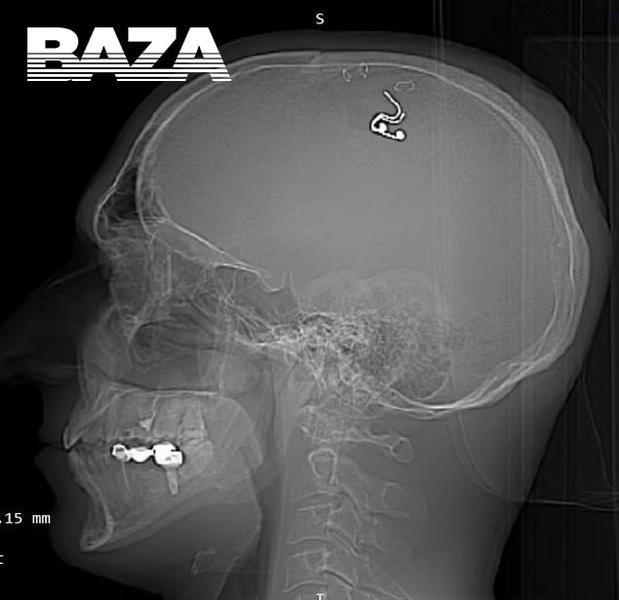

В Алмате мужчина из Новосибирска провел эксперимент и чипировал свой мозг. Как пишет Телеграм-канал BAZA, он сделал это в домашних условиях. Перед этим экспериментатор изучал в интернете информацию о работе нейрохирургов. Сообщается, что он провел опыты на пяти овцах. Затем мужчина купил дрель и просверлил себе голову, вшил электрод.

Россиянин рассказал, что едва выжил, так как потерял много крови, ведь у него почти не было хирургического опыта. Мужчина пошел на этот поступок, чтобы чип помог ему контролировать осознанные сны. К профессионалам он не обратился из-за уголовных рисков и других известных событий.

Консультант-нейрохирург Алекс Грин из Оксфордского университета считает, что мужчина легко мог умереть или получить инсульт, а теперь у него есть риск развития эпилепсии. Так здоровый мужчина добровольно подпортил себе здоровье.